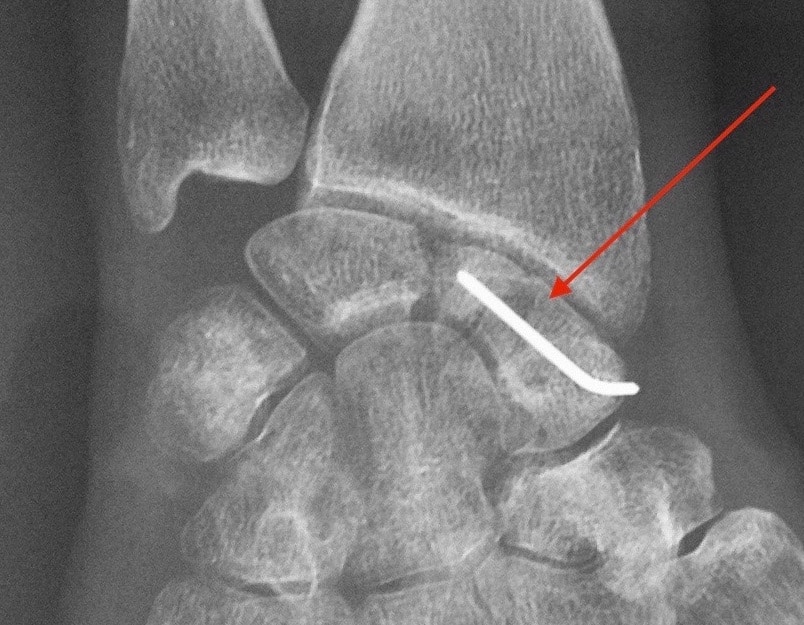

Vissage du scaphoïde

Fracture du scaphoïde

Le scaphoïde est un des os du carpe du poignet. Pièce maîtresse, véritable clef de voûte du poignet, il peut être le siège de fracture à la suite d’une chute sur la main. Cette fracture, peu douloureuse, passe parfois inaperçue ou est assimilée à une entorse et le patient ne consulte pas de spécialiste. Le diagnostic exige des clichés radiographiques à 15 jours d'intervalle, ou un scanner, qui permet plus sûrement de confirmer la fracture du scaphoïde.